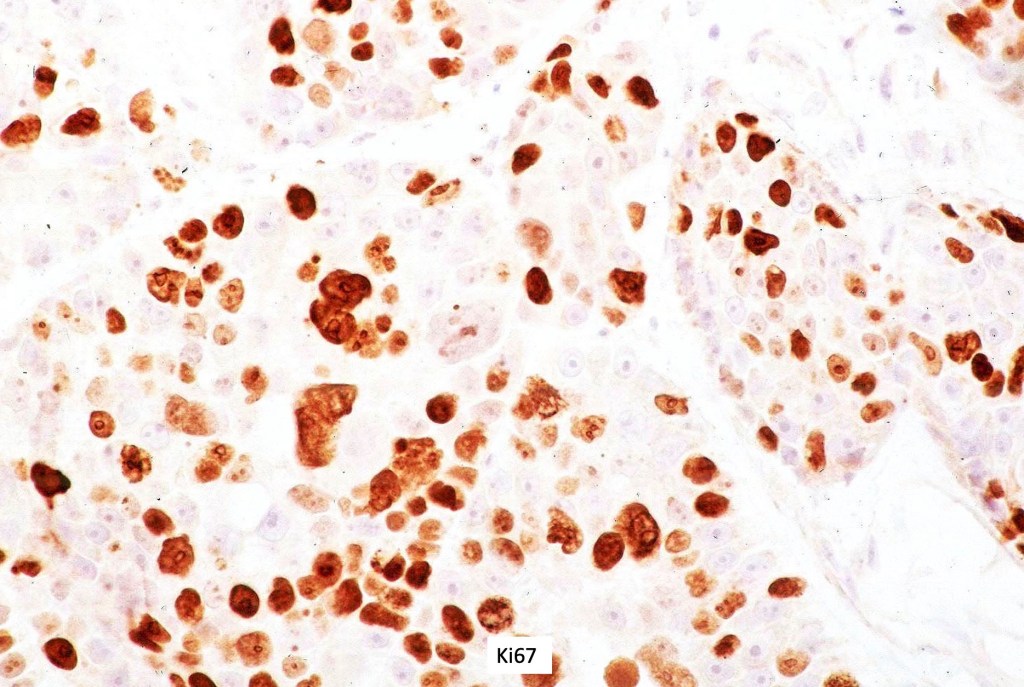

•Lobular or a diffusely infiltrating growth pattern. Composed of pleomorphic hyperchromatic, basaloid cells with nucleolar prominence, abundant mitoses & atypical mitoses (brisk mitotic activity should not be used as a defining feature of matrical carcinoma since in the evolving phase mitoses are typically very numerous in pilomatricoma)

•The basaloid cells show strong nuclear & cytoplasmic expression of beta catenin